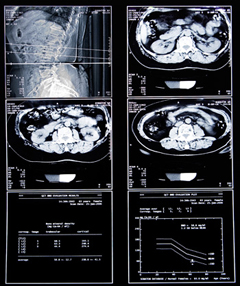

Компьютерная томография незаменима для диагностики, т.к. в результате ее проведения получается трехмерное изображение высокого качества, она позволяет сделать срезы внутренних органов размером 0,5мм и выявить незначительные изменения органов брюшины, которые невозможно увидеть на других обследованиях.